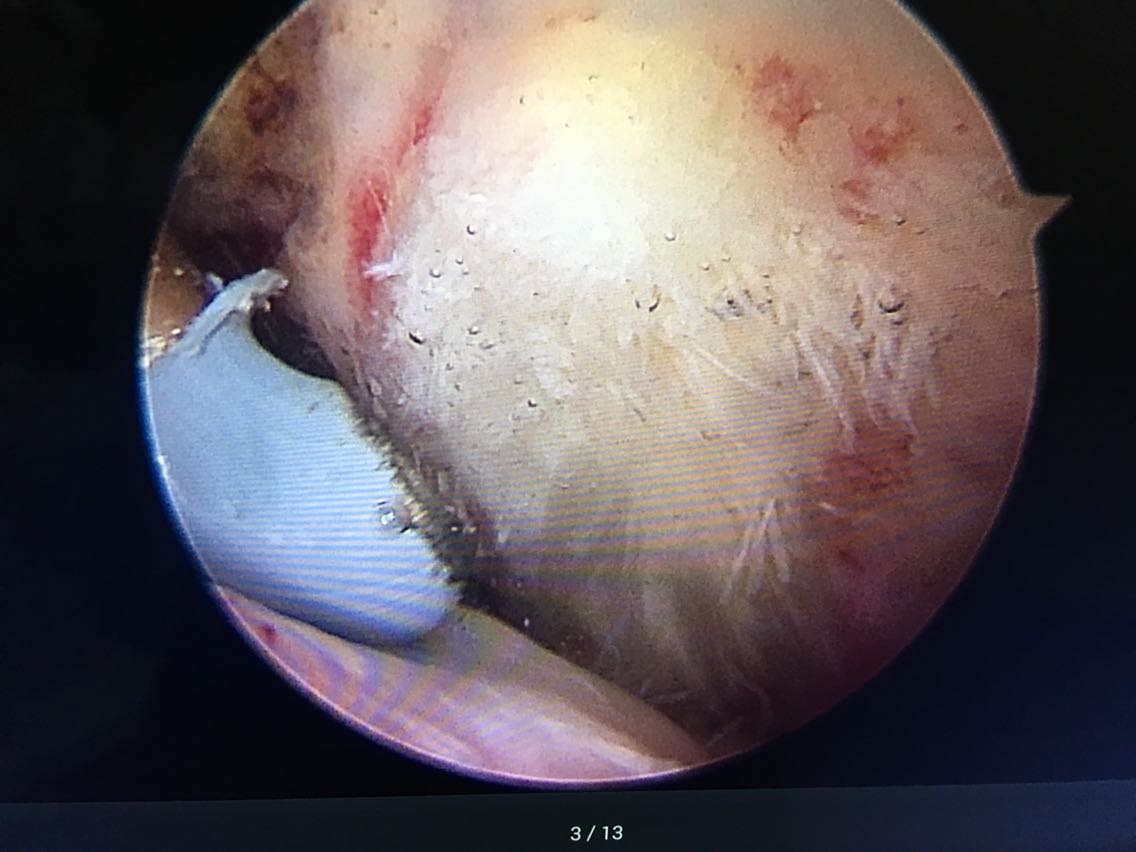

主诉:右肩关节疼痛、功能障碍6个月 现病史:患者于6个月前出现肩关节疼痛,以夜间明显,在当地医院诊断为肩周炎,给予指导关节功能锻炼,疼痛症状和功能障碍加重,效果不佳,来院就诊,核磁共振检查后,诊断为:肩袖撕裂 肩峰撞击症。收入院行关节镜下清理 肩峰成形 肩袖撕裂修补手术。

诊断:右肩袖撕裂 肩峰撞击症 冻结肩 治疗:关节镜下清理 肩峰撞击成形 肩袖撕裂修补手术。